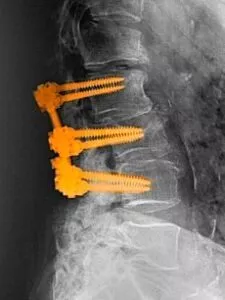

During a spinal fusion procedure, the surgeon makes an incision and then places bone graft material, either from the patient’s own body or from a

donor, between the remaining vertebrae. Metal plates, screws, or rods may also be used to hold the vertebrae in place while the bone graft material fuses them together over time.6

Next, the surgeon roughens the vertebrae to produce faster healing. In this procedure, the body replaces old bone with new. Eventually, the new bone fills the space between the vertebrae and fuses them together. Additionally, the metal implants or instrumentation, including rods, screws, and hooks or wire made of titanium or cobalt chromium, are secured to the vertebrae. All these things help to straighten and support the spine while fusion takes place.8

Lumbar Spine with Spinal Fusion Hardware.